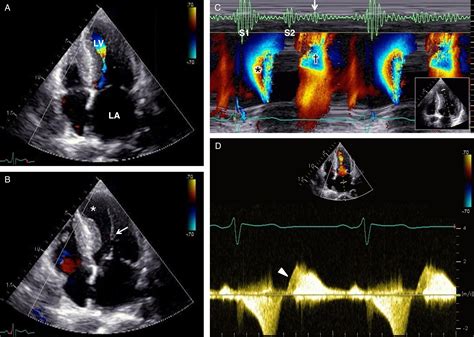

• Echocardiogram: This ultrasound test provides detailed images of the heart's structure and function, helping to identify obstructions and murmurs.